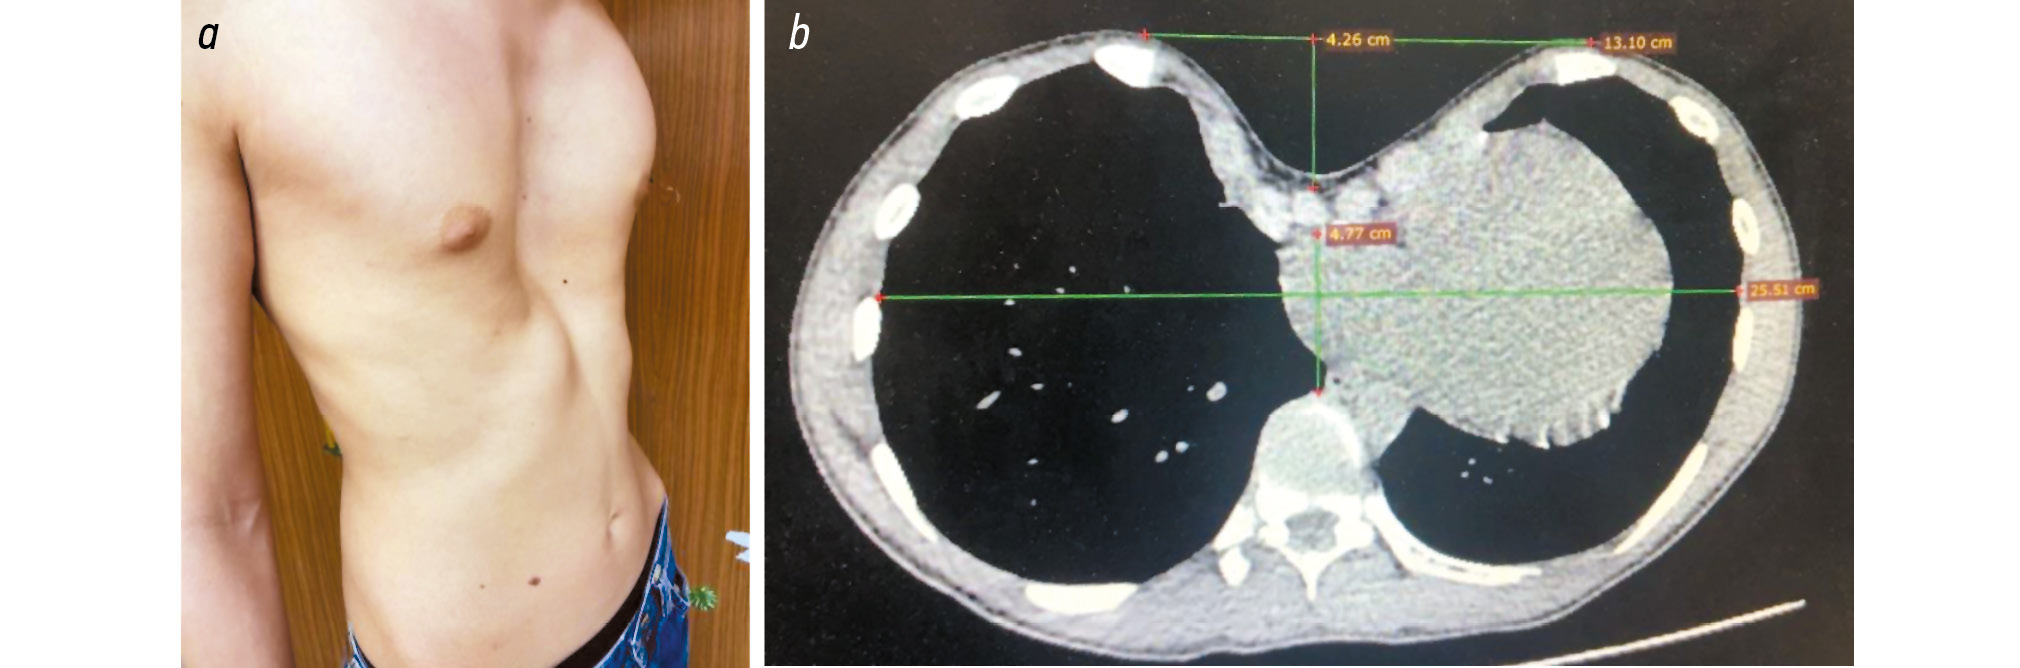

В одном наблюдении у пациентки 11 лет с ВДГК после стернотомии возникло жизнеугрожающее осложнение в виде кровотечения из-за ранения сердца во время торакоскопии. Интраоперационно выполнялась элевация грудины при помощи ВК. Во время рассечения спаек переднего средостения и мобилизации сердца от внутренней поверхности грудной стенки возникло кровотечение из дефекта стенки правого предсердия. Ушить возникший дефект не представлялось возможным. В связи с этим выполнена рестернотомия и дефект стенки правого предсердия был ушит (рис. 9). Далее установлена корригирующая пластина и выполнена коррекция ВДГК. Кровопотеря составила 900 мл, интраоперационно проводилась гемотрансфузия.

Рис. 9. Интраоперационная картина после рестернотомии и ушивания дефекта стенки правого предсердия.